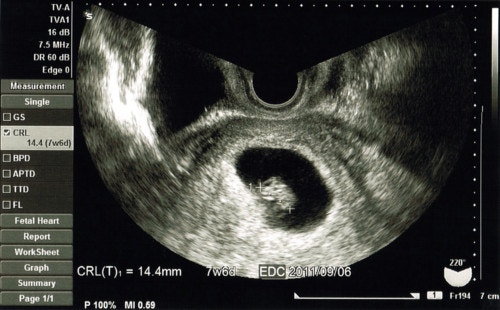

検査結果はすぐその場でわかります

モニター画面は見えるように設置してあり超音波検査して英語で説明しながら

こんな感じの写真を何枚か取って終了です